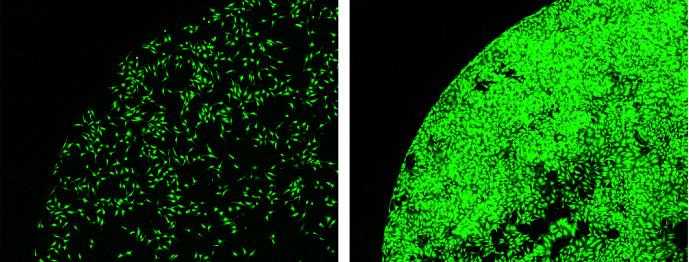

Left: Before incubation. Right: After 68 hours of incubation. Image Credit: Yokogawa Life Science

A stage incubator is provided as usual. Users can implement nonstop, long-duration observation (3 days or more) using humidity, temperature, and CO2 control.